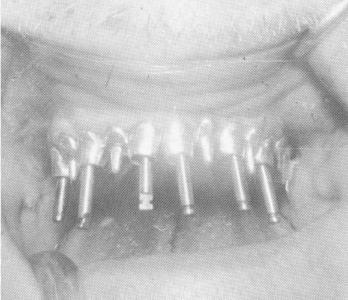

Fig. 10-256. The burs were used with the template in place.

Fig. 10-257. The implants were screwed into position. Their ends should not extend beyond the occlusal rims of the tubes.

Fig. 10-258. The vent-plants are seen to be closely parallel to one another.

Fig. 10-259. The template was locked to the protruding vent-plant shafts with a mix of cold cure acrylic resin.

Fig. 10-260. Pin implants were then drilled through the double railed portion of the template that existed posteriorly on both sides and secured to it with acrylic. All excess acrylic was carefully trimmed so it did not extend occlusally beyond any portion of the occlusal rims of the template.

3 Burs used with maxillary template in place

4 Ventplants in maxillary arch are closely parallel to one another

5 Dental pin implants drilled through template`s double railed portion